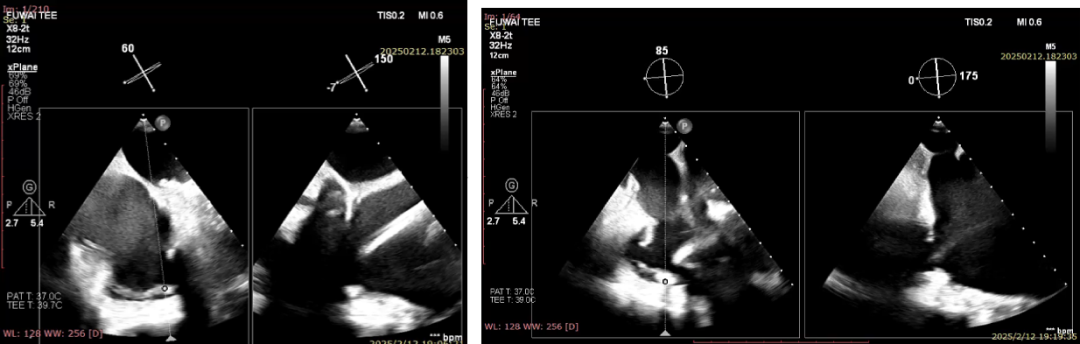

术中超声影像

输送系统调弯进入右心房

跨瓣并调整同轴性及深度

确定夹持件在位

释放瓣膜裙边并进行位置调整

室间隔锚定

解离脱钩释放瓣膜